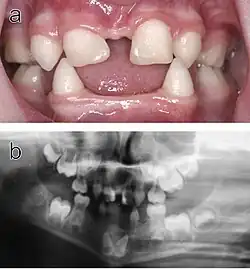

Echte Hypodontie: Die oberen seitlichen Schneidezähne sind nicht vorhanden.

Vorgetäuschte Hypodontie: Obwohl im Unterkiefer der 7er bereits fehlt, ist der 8er retiniert und scheint somit nicht vorhanden.